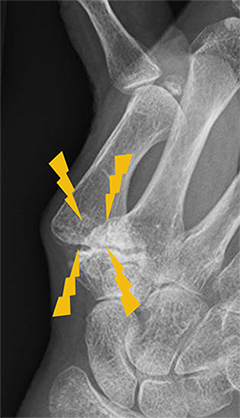

軟骨が減り、変形している母指CM関節